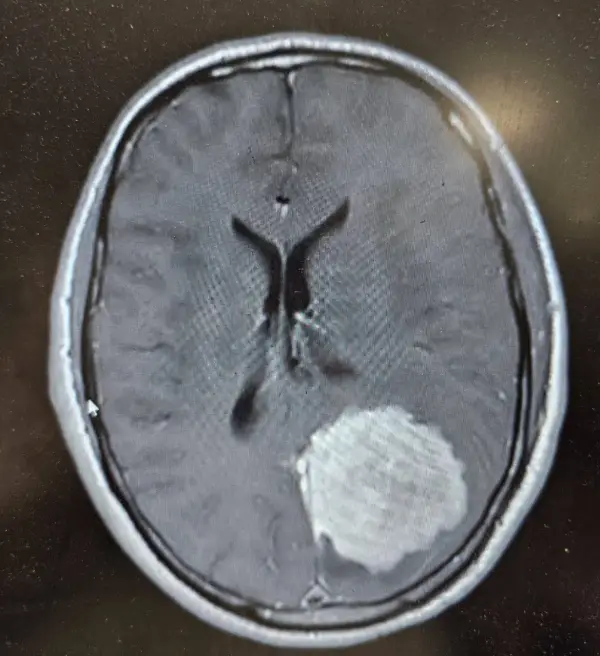

نمونه بارز عدو شود سبب خیر:

ایشون تو خیابون دعوا میکنه و سرش ضربه میخوره ، میره بیمارستان سیتیاسکن میگیره و دکترا متوجه میشن که تومور داره.